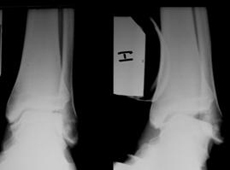

La inestabilidad de tobillo aparece cuando se rompen los ligamentos que estabilizan el tobillo. Los ligamentos que estabilizan el tobillo son: ligamento lateral externo, ligamento lateral interno y sindesmosis. El ligamento cicatriza correctamente si no hay incongruencia articular. El tratamiento conservador se aconseja en las lesiones agudas si el estudio radiológico muestra congruencia articular del tobillo.

La cirugía se aconseja cuando hay incongruencia articular en las lesiones agudas y cuando hay inestabilidades crónicas. En las lesiones agudas es preciso colocar el ligamento en la posición adecuada y suturar los ligamentos rotos. En las lesiones crónicas se realiza un retensado del ligamento si solo hay una elongación. Cuando no es posible retensar el ligamento, se utiliza alguna estructura biológica (tendón propio o de banco de tejidos) para que realice las funciones del ligamento roto. Nuestro equipo le aconsejará la operación que mejor se adapta a sus necesidades.